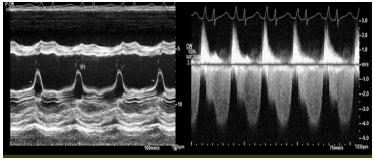

Paciente masculino de 47 anos, admitido com dor torácica e insuficiência cardíaca aguda.

Considerando a foto acima, sobre a causa da descompensação clínica, assinale a afirmativa correta.